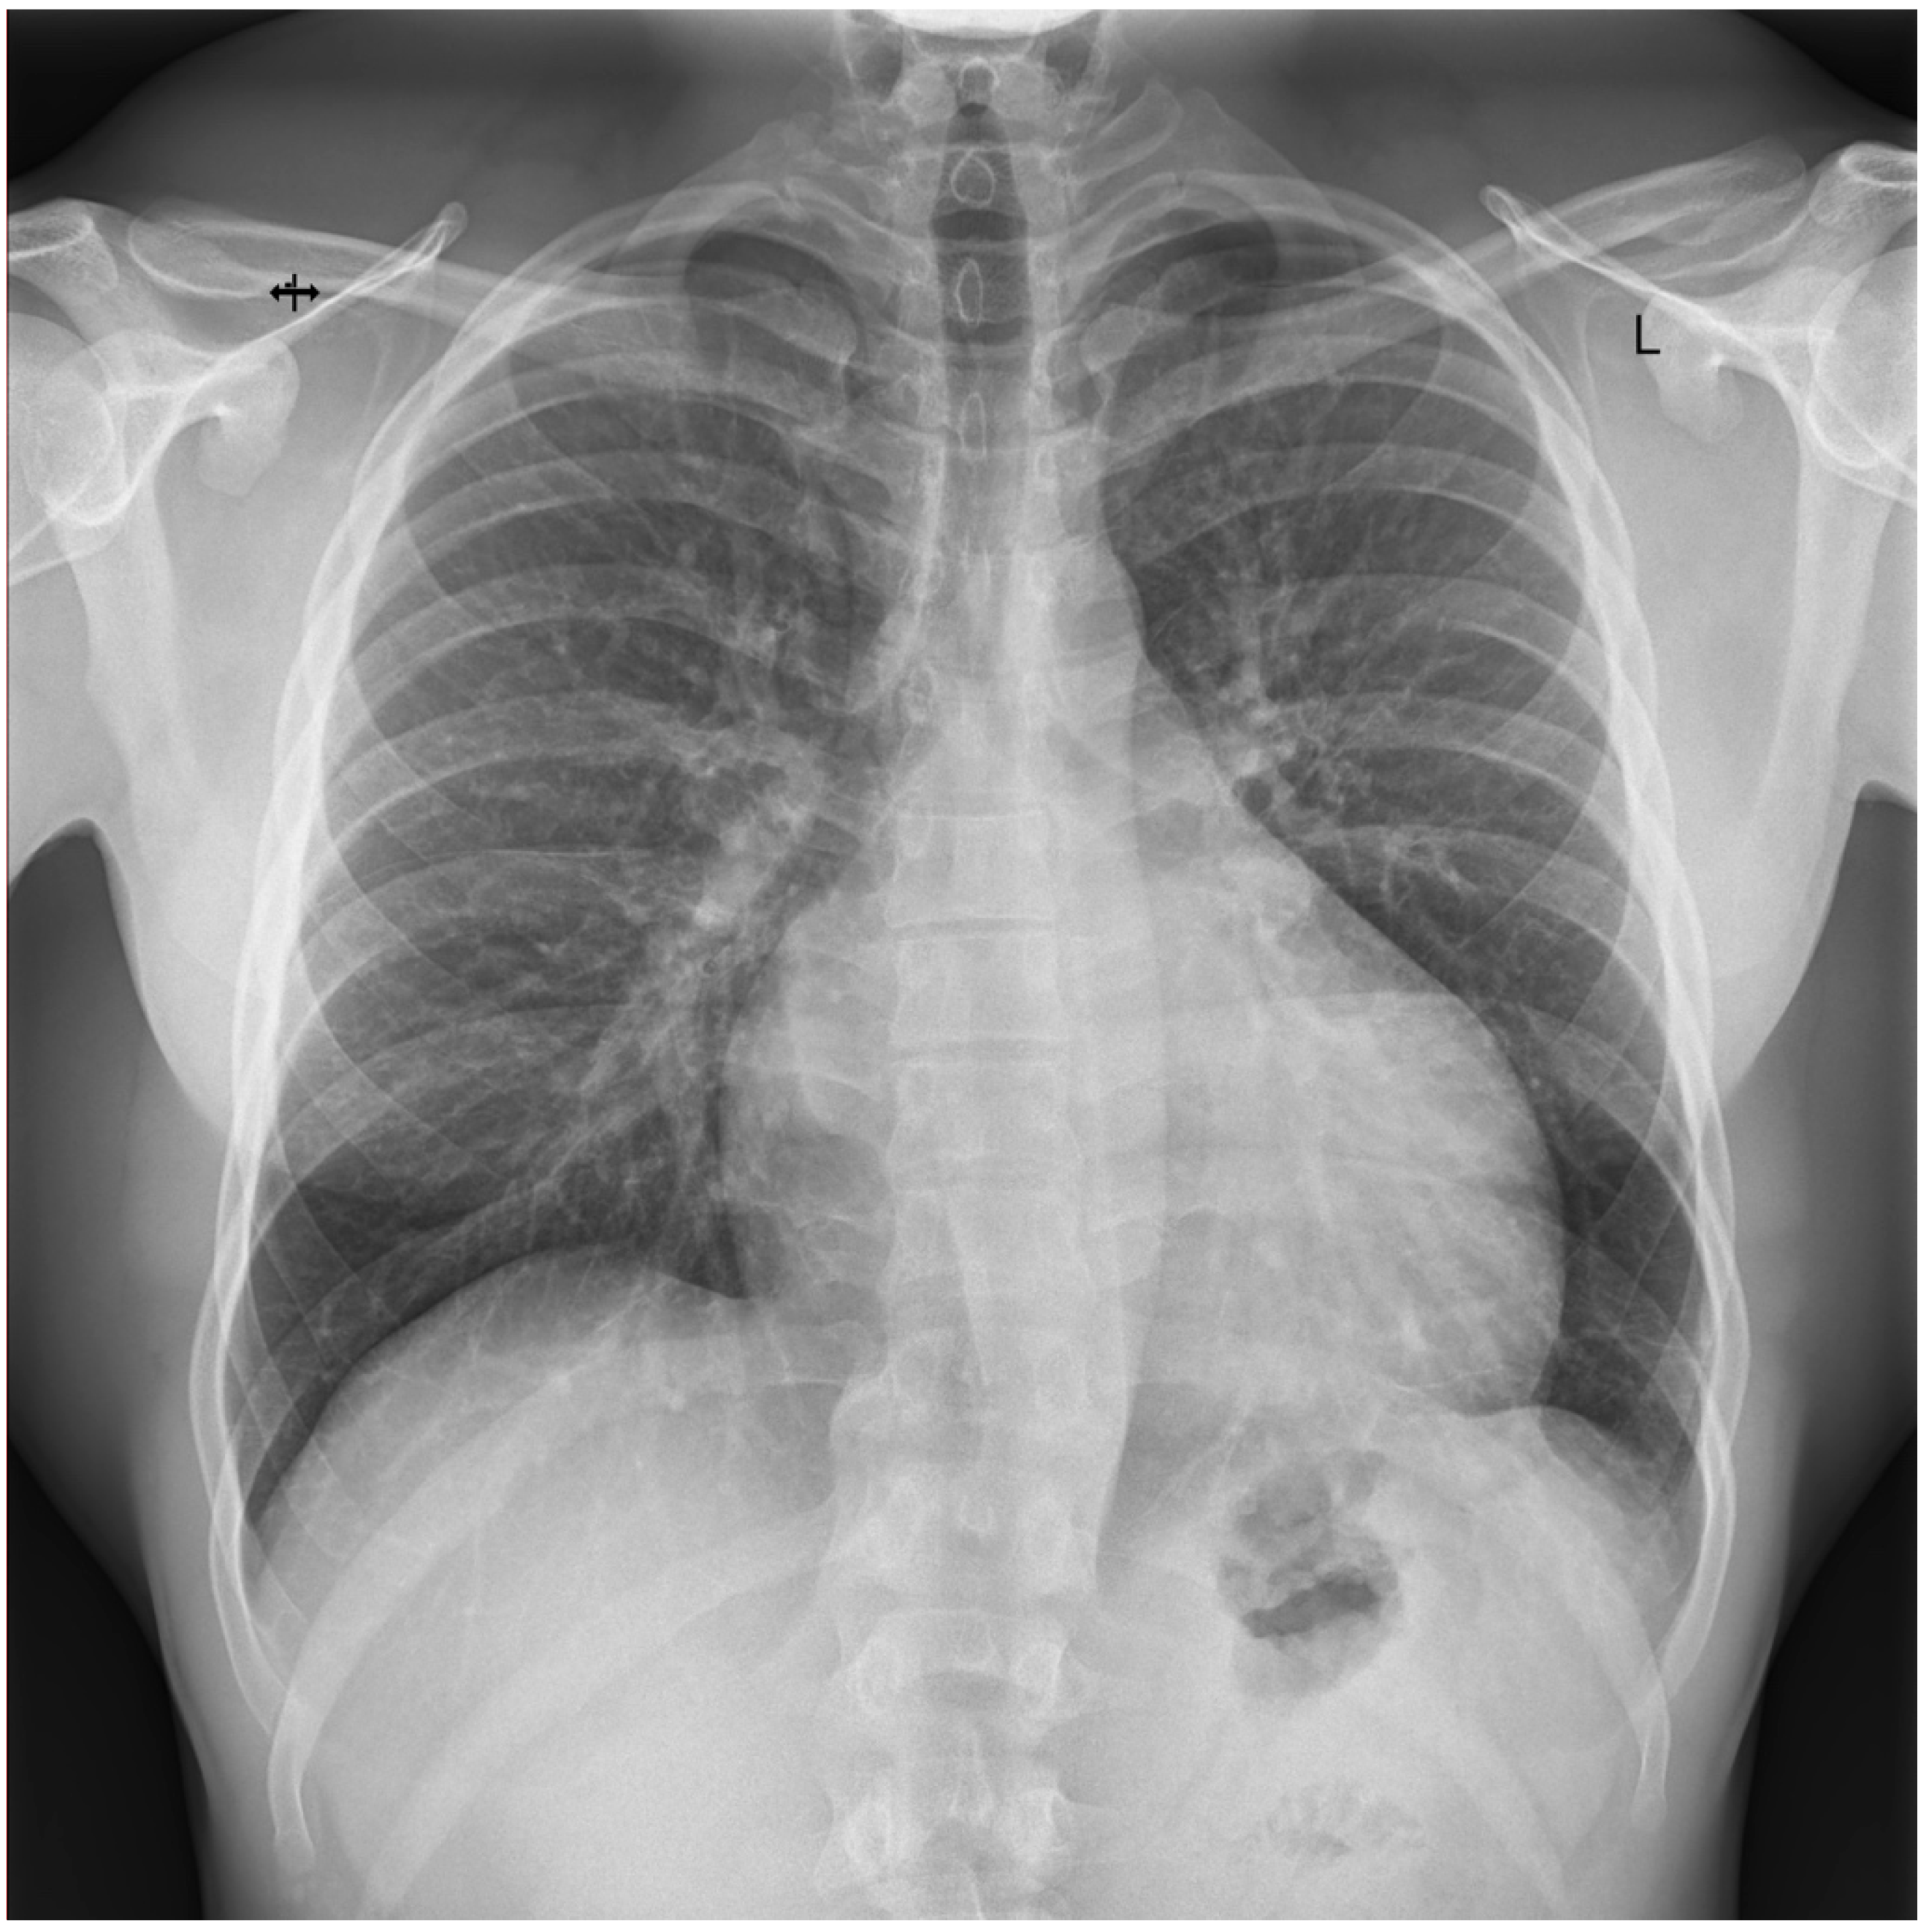

3.1. Case 1